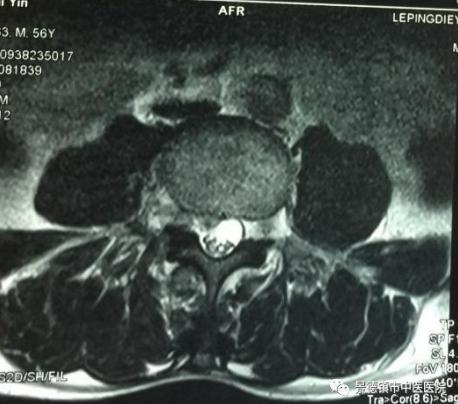

入院時患者不能行走,輪椅推入病房,查體主要表現(xiàn)為腰痛及右側(cè)臀區(qū)、大腿外側(cè)、小腿前外側(cè)的牽涉痛,直腿抬高約25°,加強(qiáng)實驗陽性,腰椎MRI提示為L4/5節(jié)段椎間盤后上突出。

上圖為:MRI提示L4/5中央偏右并向上的椎間盤突出,黃韌帶增生肥厚